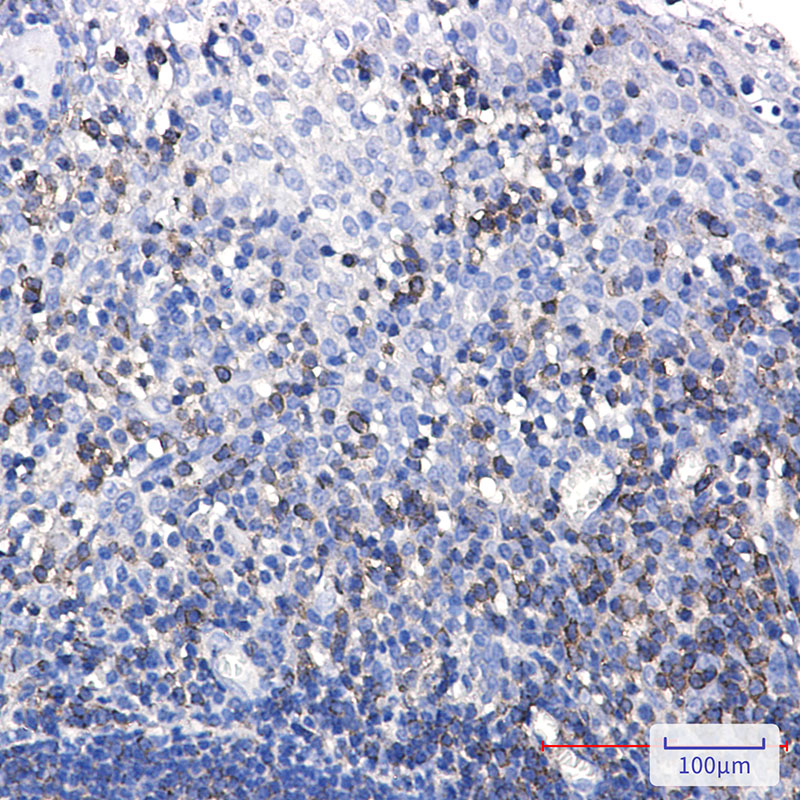

IHC 1/50-1/100 Human,Mouse,Rat

**摘要**:研究者开发了一种高特异性的SHP1单克隆抗体,验证了其在石蜡包埋组织中的免疫组化适用性,并发现SHP1在部分白血病样本中表达显著降低,提示其作为潜在诊断标志物的价值。